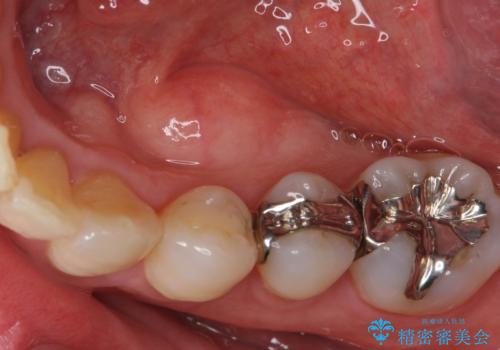

- メンテナンスでいらっしゃった患者様です。

歯を保護するためのナイトガードを装着していきます。

厚みのあるナイトガードを調整することで、夜間の歯ぎしりにより歯にかかる強い力を分散させることができます。